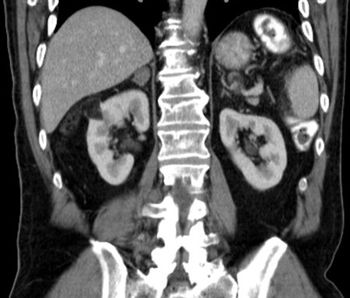

A reduced estimated glomerular filtration rate (eGFR) was found to be associated with a significantly increased risk for renal and urothelial cancer, according to the results of a recently published study.